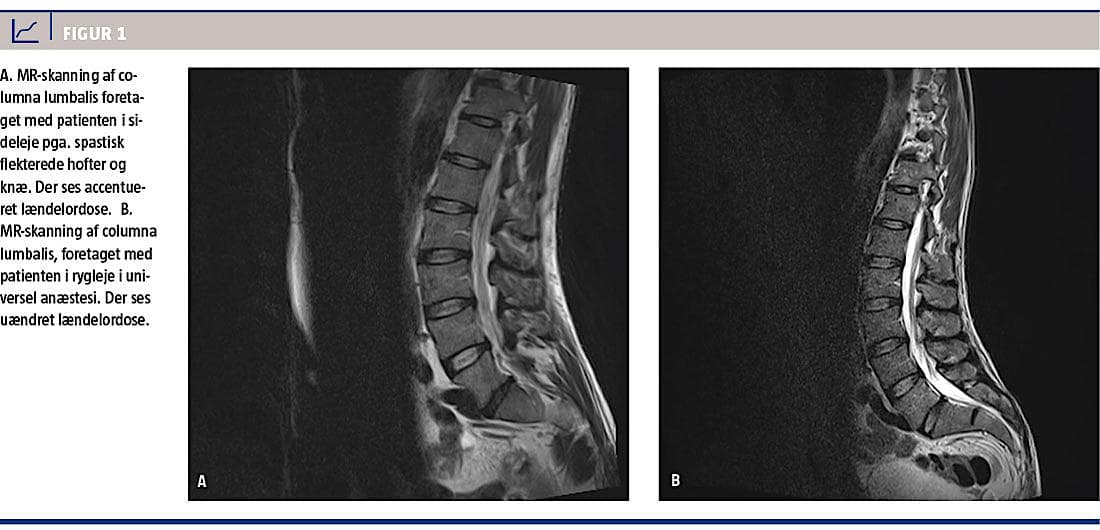

I august 2013 blev en 46-årig mand indlagt på en reumatologisk afdeling med progredierende lænde-hofte-smerter og immobilitet. Han var i øvrigt sund og rask, men havde i december 2012 været ude for et glatføretraume, hvor han gik i spagat. Siden da opstod der, især i tilslutning til fysisk aktivitet, periodevise, men tiltagende lænde-hofte-smerter, kramper og stivhed, hvilket resulterede i immobilitet. I måneder op til indlæggelsen var han ude af stand til at gå oprejst. Ved klinisk undersøgelse fandt man på trods af accentueret lumbal lordose (Figur 1) en foroverbøjet gangfunktion med næsten 90 graders hofte- og knæfleksion og tågang. Der var normale neurologiske forhold. Forsøg på passiv udretning af benene udløste modstand over hofter og knæ med ledsagende stærke smerter. Om natten var knæ og hofter udrettede. Behandling med gængse analgetika og muskelrelaksantia var uden effekt. Ved neurologisk vurdering fandt man ingen tegn til neurologisk lidelse. Ved en MR-skanning af columna totalis påvistes der primært degenerative forandringer. En CT af thorax og abdomen og MR-skanning af cerebrum var upåfaldende. Biokemisk fandt man normale forhold, fraset let forhøjede niveauer af basisk fosfatase og laktatdehydrogenase. Ved en neurologisk second opinion på højtspecialiseret niveau konkluderede man, at tilstanden var traumatisk betinget og af muskulær genese. dersøgelser i form af elektromyografi og elektroneurografi viste upåfaldende forhold. Patienten blev viderehenvist til tenotomi af psoas, rectus femoris og sartorius bilateralt på en kirurgisk afdeling og efterfølgende fysioterapi, hvorved han opnåede langsom bedring med udretning over hofter og knæ, men han havde fortsat trippende tågang.